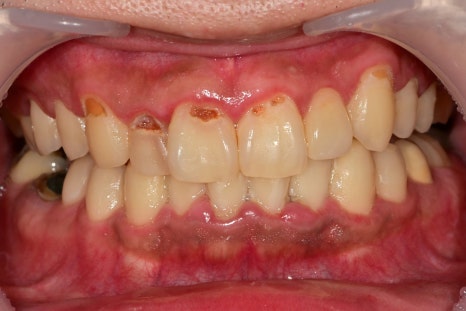

치아와 잇몸 경계부에 플라그(치태)가 쌓이게 되면서

제거가 잘 안되다 보니 주변 잇몸이 빨갛게 붓고

다발성 충치가 유발된 상태였습니다.

앞니 쪽은 양치하기가 쉽다고 생각을 하기 때문에

종종 앞니 쪽 잇솔질을 빠르게 넘어가는 일이 생깁니다.

대부분 놓치는 부분이 잇몸과 치아의 경계 부위, 치아 사이입니다.

잇몸치료와 충치치료가 완료된 사진입니다.

치아 사이 충치가 생긴 어금니는 충치가 깊어 신경치료까지 진행했습니다.

잇몸 경계 부위 충치로 인해 치료 과정에서 잇몸에 출혈이 약간 있을 수밖에 없지만

금방 회복되며, 앞니 쪽이라 기존 치아의 색상에 맞춰

레진 치료를 이쁘게 진행해 드렸습니다.^^